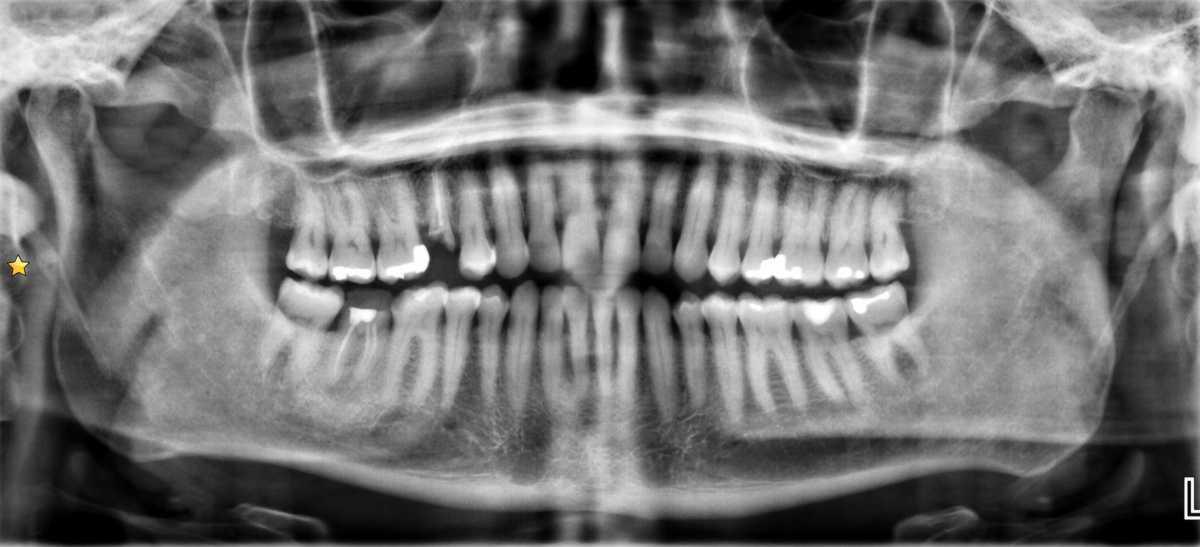

Daniel J Bell, Radiopaedia.org. From the case rID: 150571

Radiographie panoramique dentaire puis hospitalisation dans le service de chirurgie maxillo-faciale pour prise en charge au bloc opératoire dans les 24H.